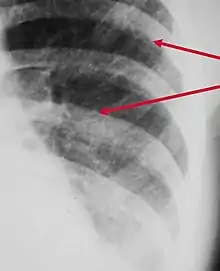

Peribronchial cuffing, also referred to as peribronchial thickening or bronchial wall thickening, is a radiologic sign which occurs when excess fluid or mucus buildup in the small airway passages of the lung causes localized patches of atelectasis (lung collapse).[1] This causes the area around the bronchus to appear more prominent on an X-ray. It has also been described as donut sign, considering the edge is thicker, and the center contains air.